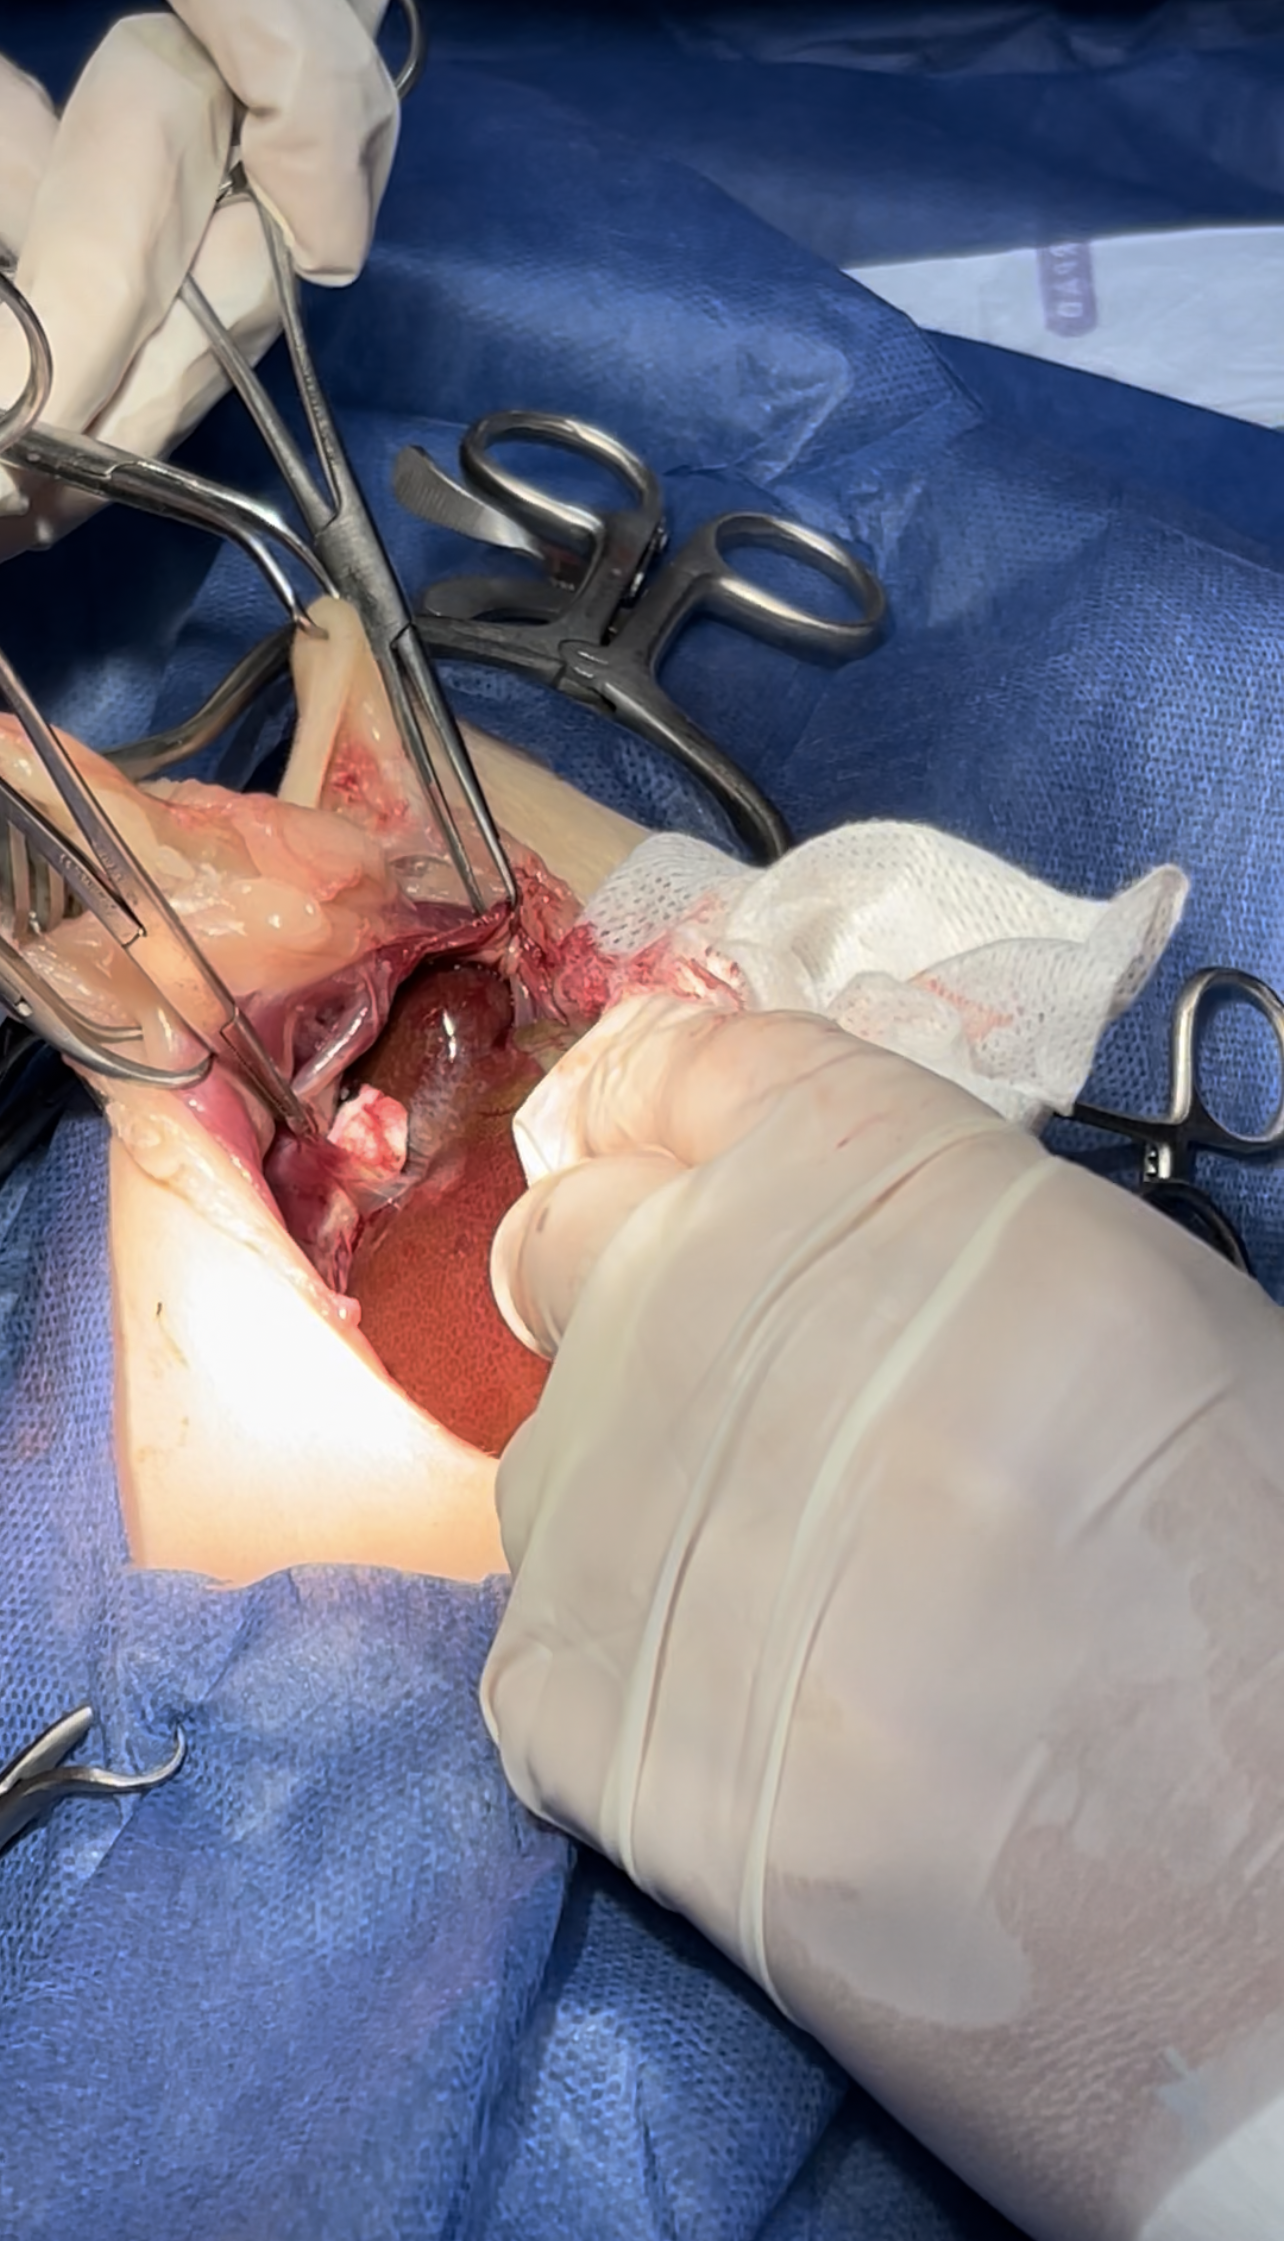

Dissection of the intraabdominal adhesive part of the live

Widening the herniation to allow organ exteriorization